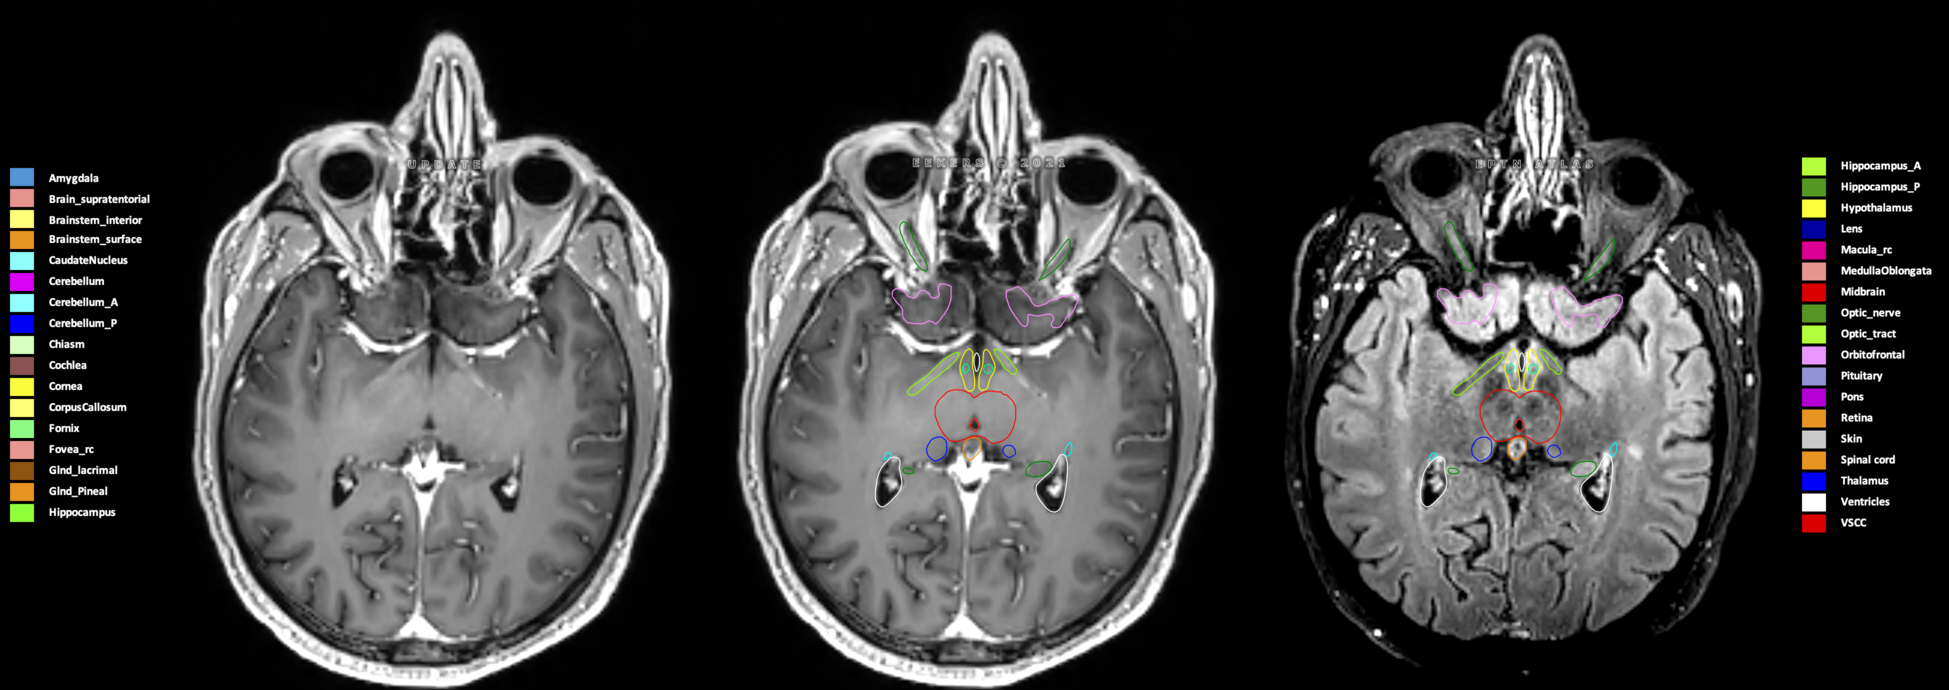

Eekers et al. have published an international neurological atlas for contouring of organs at risk in consensus with the European Particle Therapy Network (EPTN) in 2018 and an update in 2021. The purpose of this consensus atlas is to decrease inter- and intra-observer variability in delineating OARs relevant for neuro-oncology.

Included are all OARs known to be relevant for radiation-induced toxicity in neuro-oncology: brain, brainstem (midbrain, pons, medulla oblongata), chiasm, cerebellum (anterior & posterior), cochlea, cornea, hippocampus (anterior & posterior), hypothalamus, lens, lacrimal gland, optic nerve, pituitary, skin, and vestibular & semicircular canals. To further facilitate research on cognition, vision and radiological changes after irradiation of the brain, potential clinically-relevant OARs are included: amygdala, caudate nucleus, cerebellum (anterior & posterior), corpus callosum, fornix, macula, optic tract, orbitofrontal cortex, periventricular space (PVS), pineal gland, and thalamus.

Three-dimensional delineation of the 25 consensus OARs for neuro-oncology are shown on CT (WW/WL 120/40, 3000/600), 3T MR images, (T1Gd, T2FLAIR 1mm) and 7T MR (MP2RAGE 0.7 mm). All are presented in transversal, sagittal and coronal view.